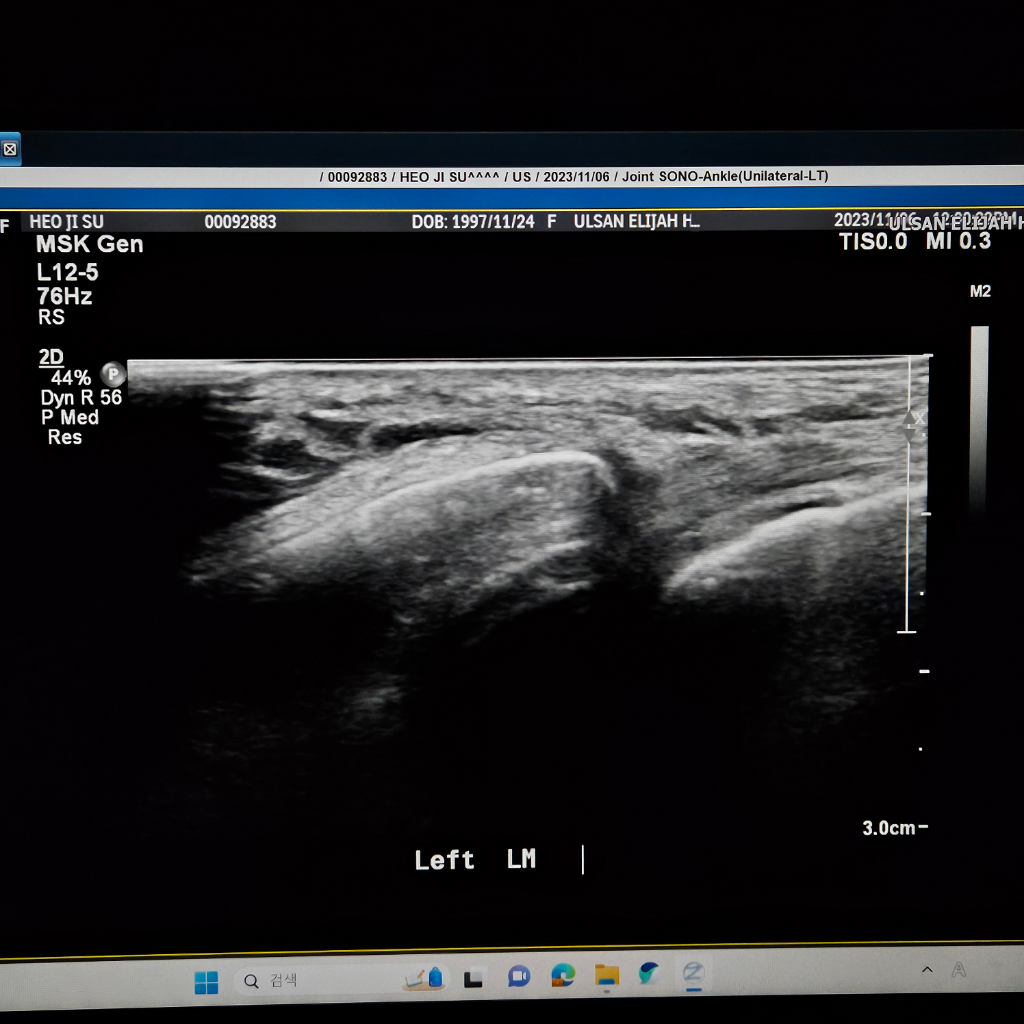

발을삐어서 병원을 갔는데 인대가 파열됬다는데 맞는지요?

발을 삐어서 병원을 갔는데 첨에 걸을때 넘아파서 못걸을정도 였습니다. 복숭아뼈 주위도 부워있었고

초음빠도 찍었습니다. 초음파에서 인대가 끈어졌다는데

끈어진게 맞나요? 첨에 수술 예기 하더니 아직 젊으니 반깁스 하고 일주일 두고보자고했습니다.

• 2번 째 사진

초음파는 실시간으로 발목을 움직여보면서 찍습니다.

검사자가 가장잘 판단을 내릴수 있습니다.

해당병원에 재문의해보세요.